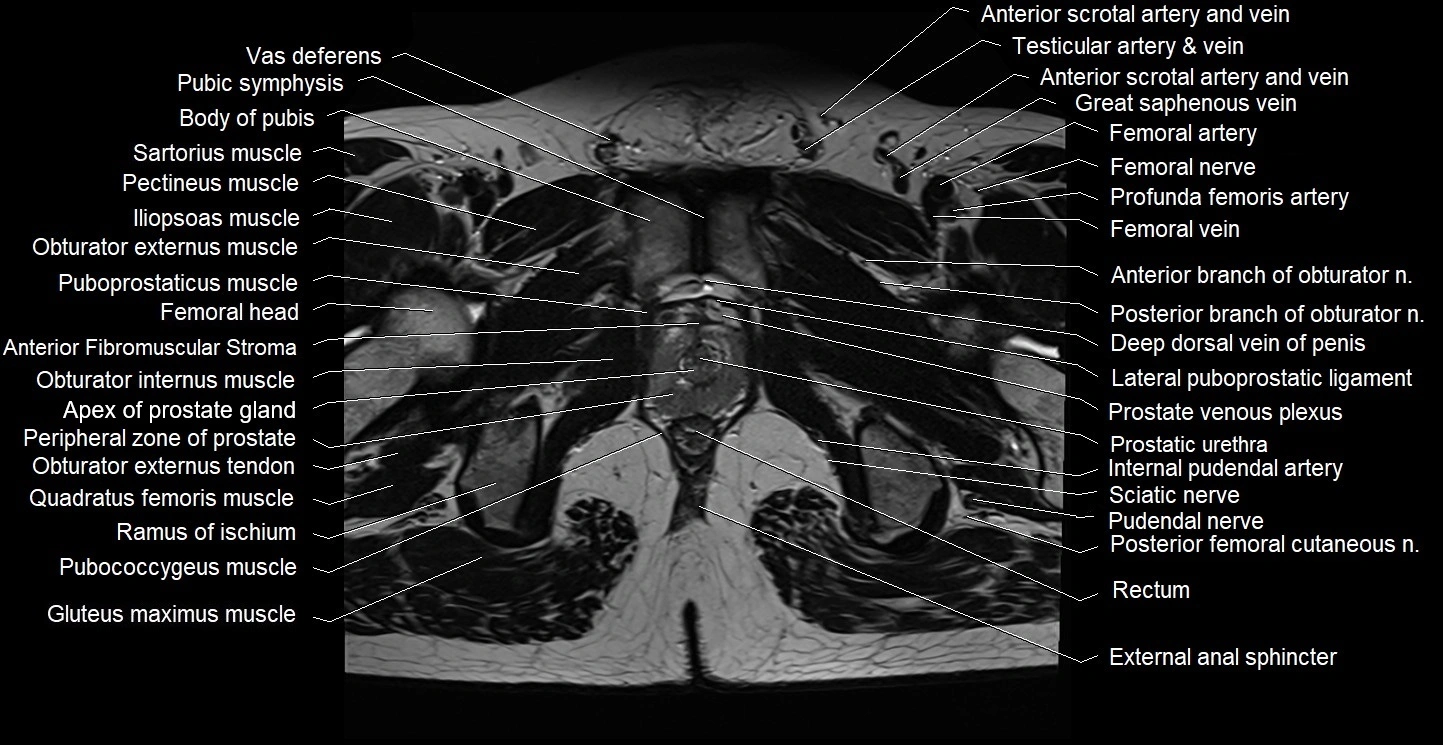

- Anterior Fibromuscular Stroma of prostate

- Body of pubis

- Deep dorsal vein of penis

- External anal sphincter

- Gluteus maximus muscle

- Iliococcygeus muscle

- Iliopsoas muscle

- Iliopsoas tendon

- Internal pudendal artery

- Obturator externus muscle

- Obturator externus tendon

- Obturator internus muscle

- Pectineus muscle

- Peripheral zone of prostate

- Posterior femoral cutaneous nerve

- Prostatic urethra

- Pubic symphysis

- Pubococcygeus muscle

- Puboprostatic ligament

- Puboprostaticus muscle

- Pudendal nerve

- Quadratus femoris muscle

- Ramus of ischium

- Rectum

- Sartorius muscle